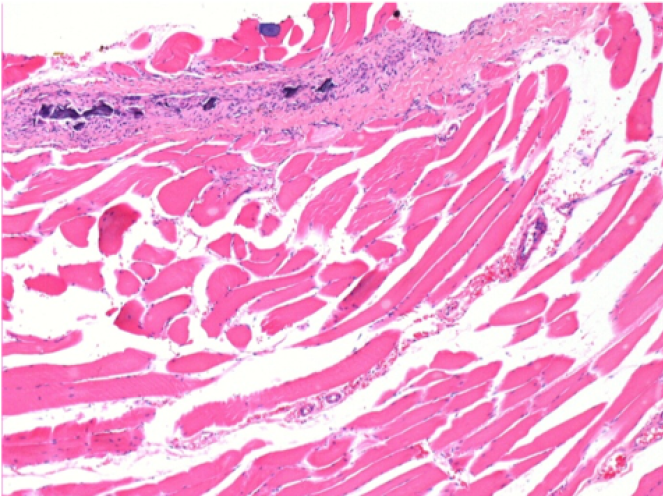

0,5 мл (5x 0,1 мл) підшкірна ін'єкція Ендопіл в праву підшкірну претибіальну ділянку.

Л:200x-Контроль-ПШ

П-10днів-ПШ-200X

П-30днів-ПШ-200X

П-90днів-ПШ-200X

П-210днів-ПШ-200X

П-210днів-ПШ-400X